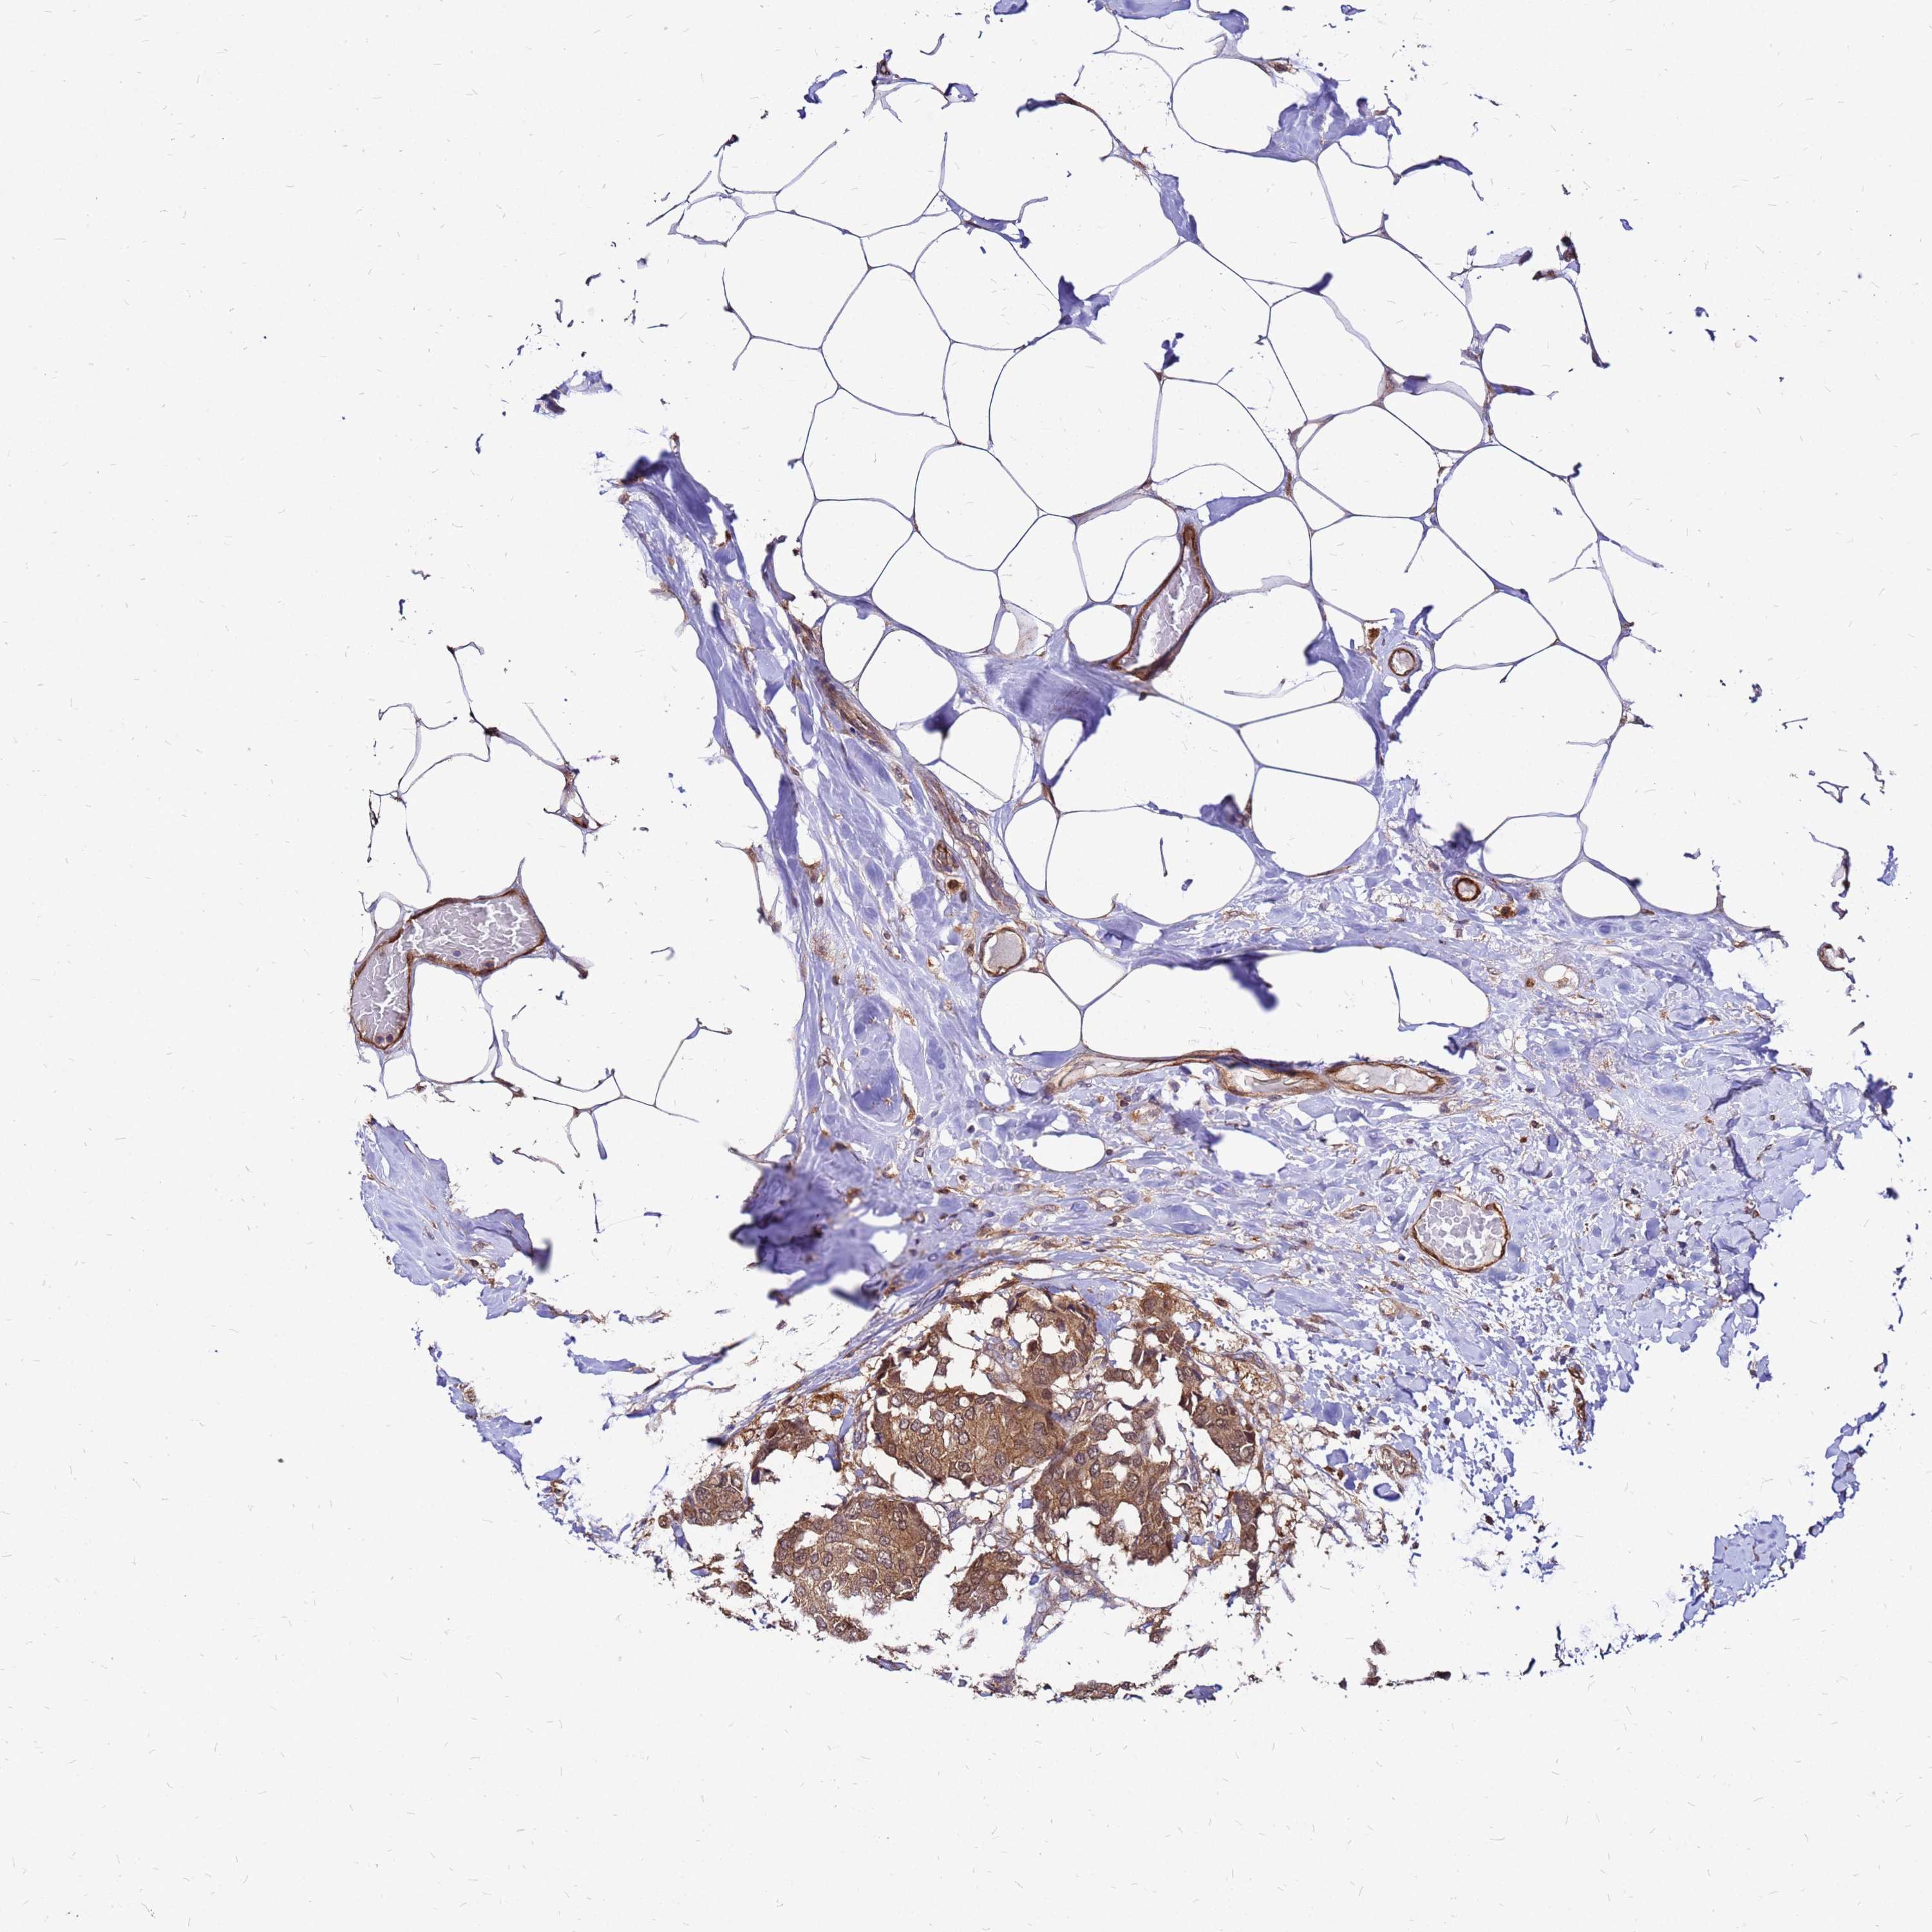

CANCER BREAST CANCER Show tissue menu

BRCA TCGA BRCA VALIDATION PROTEIN EXPRESSION

ANTIBODIES

AND

VALIDATION